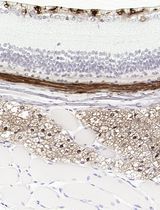

Improved Immunohistochemistry of Mouse Eye Sections Using Davidson's Fixative and Melanin Bleaching

Anne Nathalie Longakit [...] Catherine D. Van Raamsdonk